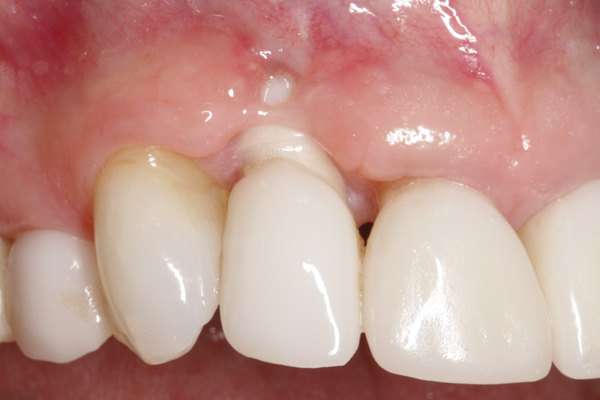

Fig 5. Atraumatic extraction without raising the flap, with the intention of minimizing bone loss, especially in the interproximal area.

Figure 5